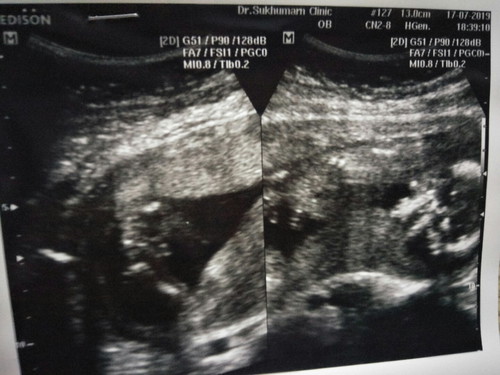

ซาวหน้าท้อง 16 สัปดาห์ หมอบอกว่าน่าจะผู้ชาย

แม่ๆบ้านไหนพอจะดูเป็นไม่คะ ว่าผู้หญิงผู้ชาย มีของใครที่หมอบอกว่าน่าจะ แล้วจากชายเป็นหญิงมั้ย รู้สึกกังวลค่ะ ท้องแรกอยากได้ลูกชาย

ผู้ชายค่ะคุณแม่